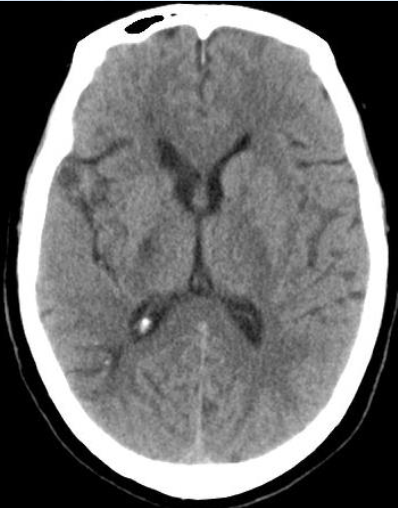

影像诊断

入院CT

病历夹什么径技·第152期|串联营病历夹:川陕大营_https://www.jmylbn.com_新闻资讯_第57张

病历夹什么径技·第152期|串联营病历夹:川陕大营_https://www.jmylbn.com_新闻资讯_第58张

<<滑动查看下一张图片>>